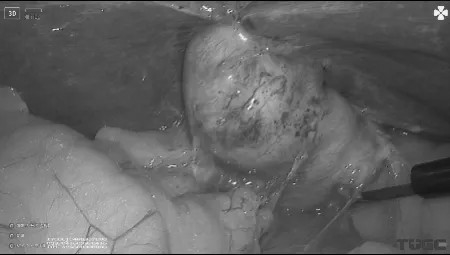

手术如期顺利进行,解剖胆囊三角后,充分显露胆囊管及胆总管前壁,用一次性结扎夹将胆囊壶腹部夹闭,施行胆囊管T字切开,用超细胆道镜经胆囊管行胆总管探查,发现胆总管下段多发结石,用取石网篮抓取,并从胆囊管取出,胆道镜探查无结石残留。随后用结扎夹双重夹闭胆囊管,常规切除胆囊。

图一解剖胆囊三角